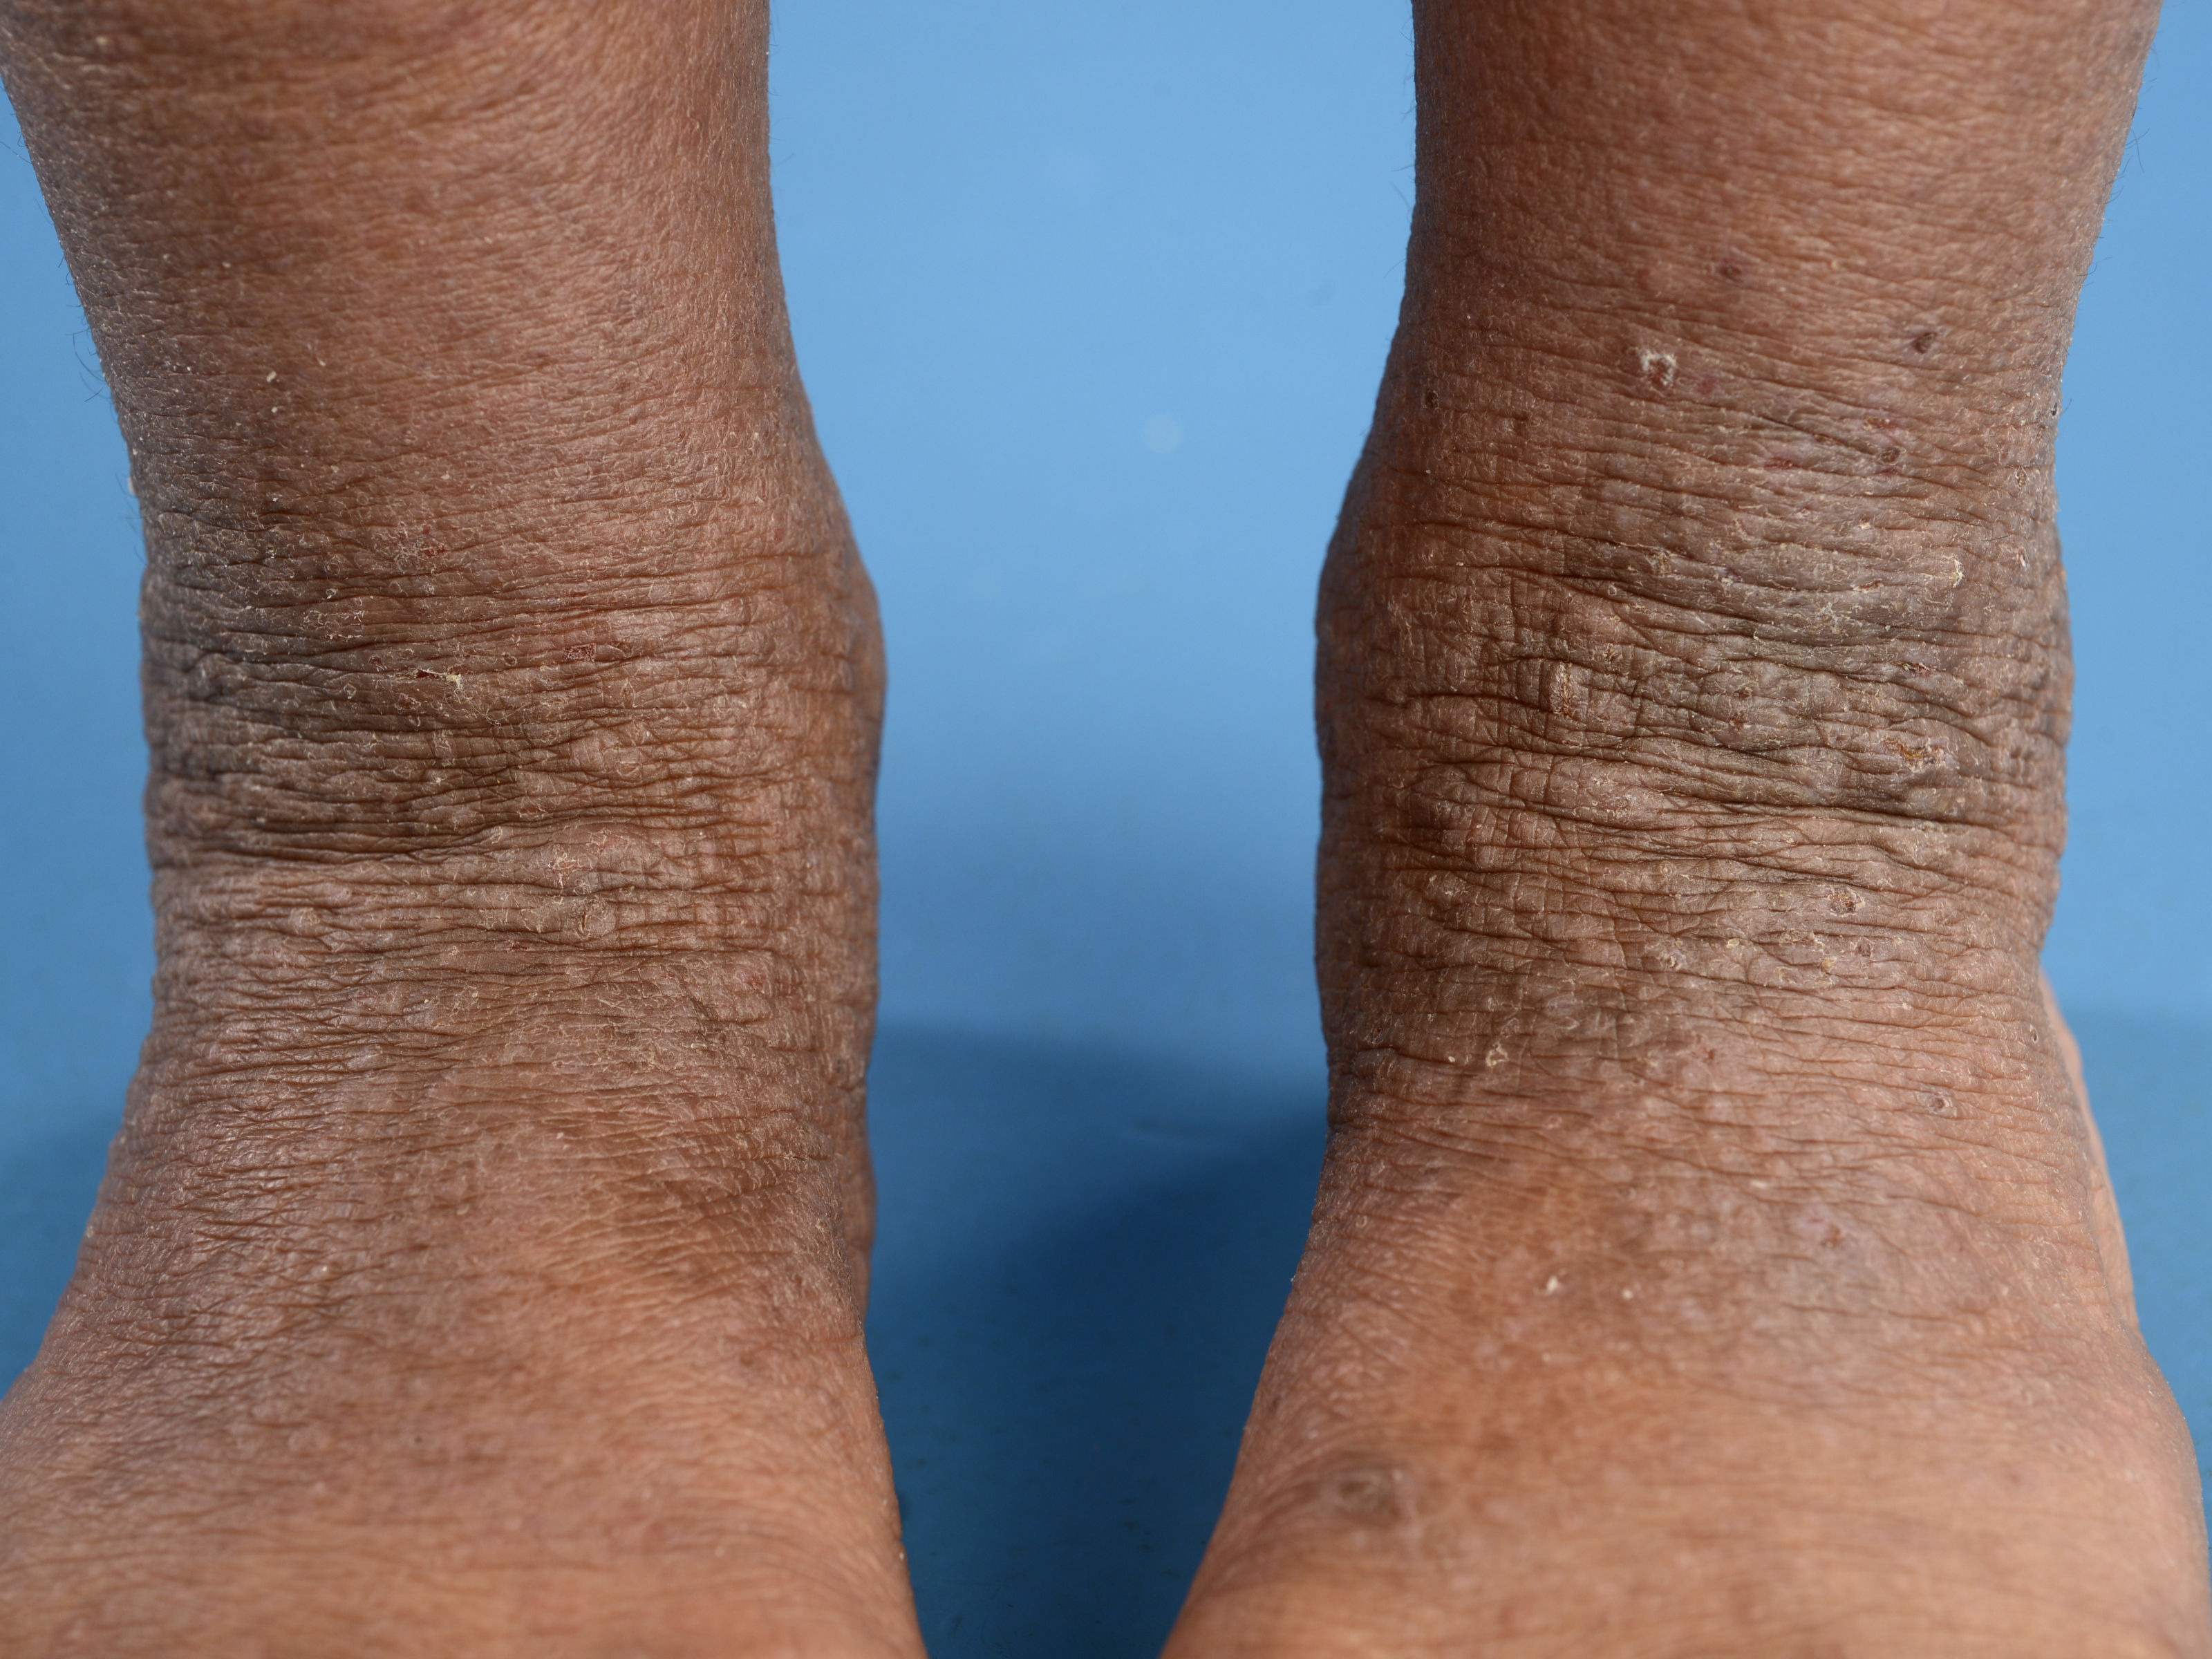

romp, extremiteiten; nattend, crusteus, jeukend. Juveniel: elleboogplooien,

knieholten, polsen, enkels; erytheem, papels, vesikels, ook droog/rhagaden/lichenificatie.

Adulte vorm van atopisch eczeem: recidieven, exacerbaties

en remissies, op strekzijde ellebogen en knieën, nek, gelaat, handen, regio

genitalis; prurigo/papels/lichenificatie, soms nattend, hevige jeuk. Bij

atopisch eczeem

bij donkere huid kan het erytheem moeilijker zichtbaar zijn, en de

klinische presentatie is soms anders, bijvoorbeeld folliculair eczeem,

papuleus eczeem, eczeem op de strekzijden in plaats van de buigzijden, meer

lichenificatie, vaker een prurigo nodularis beeld, en post-inflammatoire

hyperpigmentatie.